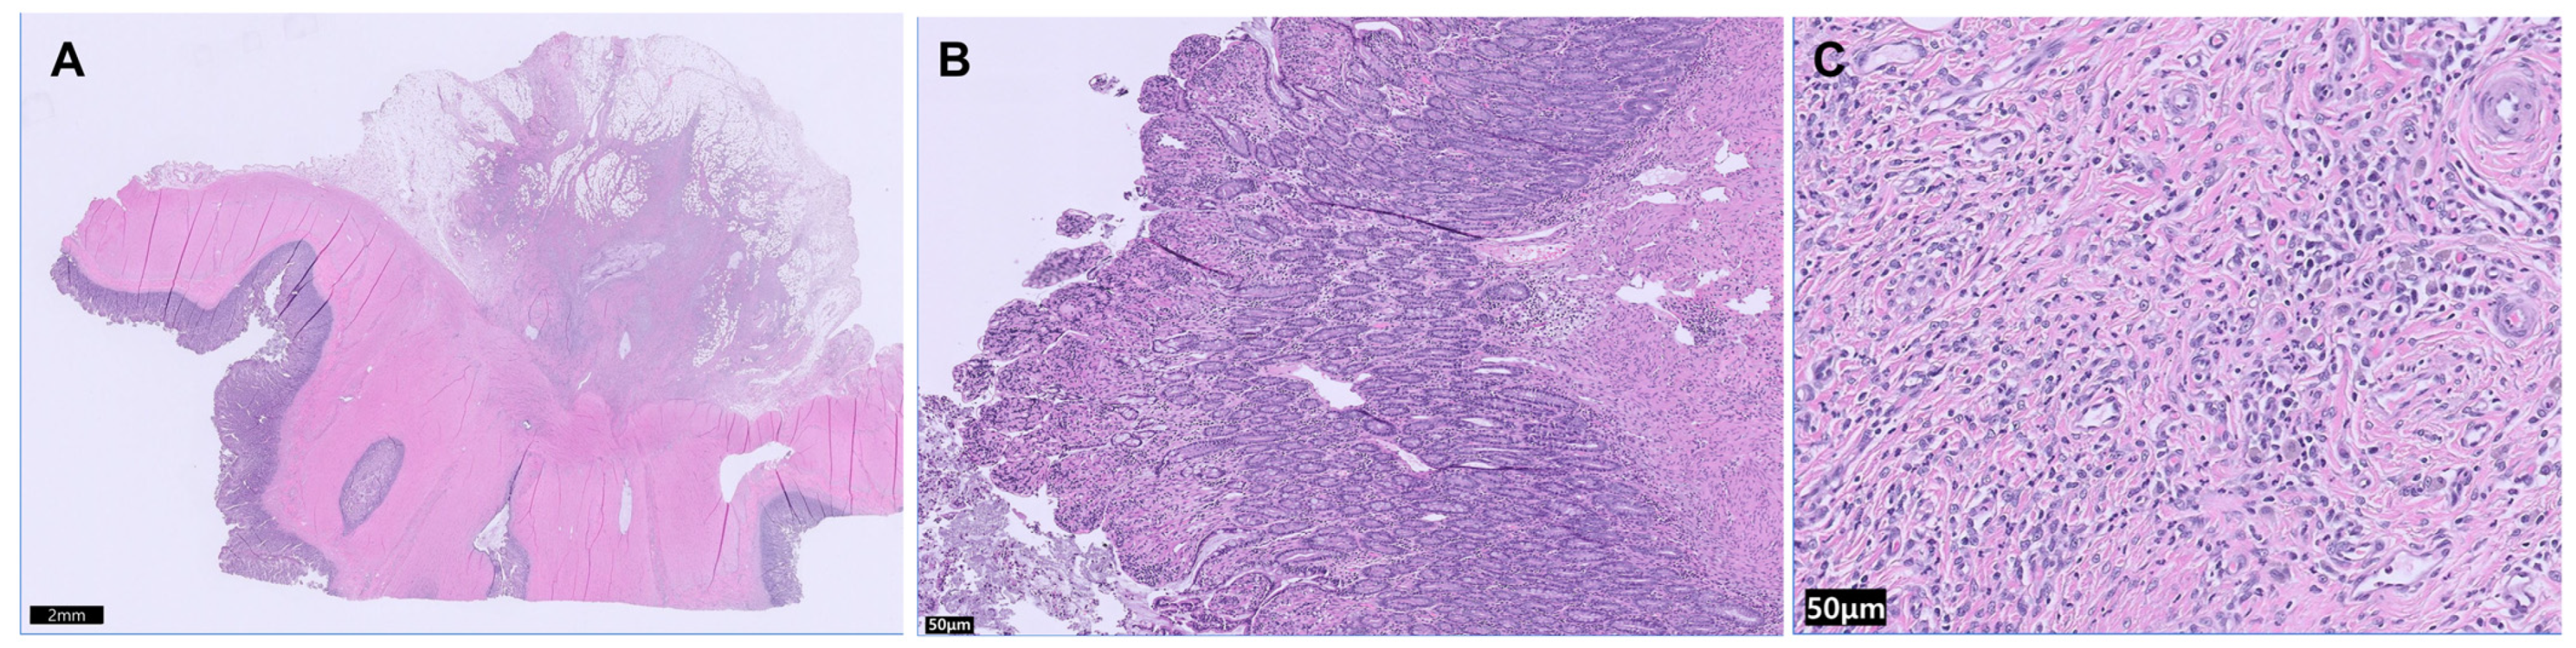

Histopathological examination of the resected ileocolic segment and associated jejunal lymph nodes established the definitive diagnosis. Microscopic evaluation revealed severe, transmural inflammation and fibroplasia involving the ileal wall. The lesion was characterized by extensive fibroplasia affecting the mural and serosal layers, with extension into the adjacent mesentery (Figure 3A). The inflammatory component consisted predominantly of lymphoplasmacytic enteritis within the mucosa and submucosa, while the mesenteric fibroplastic regions contained a mixed chronic inflammatory cell population composed primarily of plasma cells and histiocytes (Figure 3B,C).

Histopathological analysis definitively ruled out malignancy, identifying the lesion as a non-neoplastic fibrotic intestinal stricture. The excised lymph nodes demonstrated reactive lymphoid hyperplasia, consistent with chronic, non-specific antigenic stimulation secondary to the adjacent enteritis. No histopathological evidence of metastasis or primary lymph node pathology was identified in the examined tissues.

Figure 3. Histopathological and Molecular findings of the transmural ileal inflammation and fibrosis. (A) 5×, H&E, Full-thickness section demonstrating severe, transmural inflammation and fibroplasia extending into the mesentery (Scale bar = 2 mm). (B) 100×, H&E, Inflammation in the intestinal mucosa and submucosa (Scale bar = 50 μm). (C) 400×, H&E, Mesenteric inflammation and fibroplasia with dense collagen bundles and predominantly neutrophilic, plasmacytic, and histiocytic infiltrates (Scale bar = 100 μm).